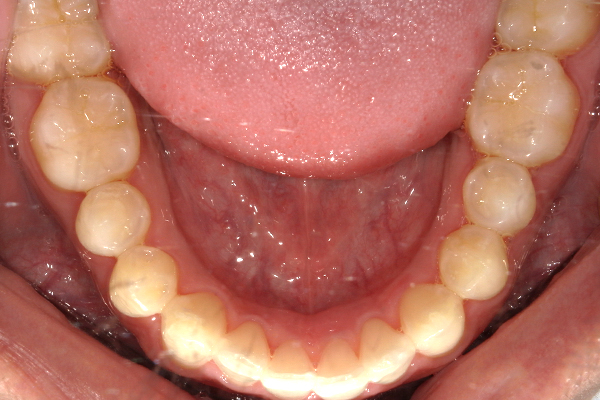

初診時の口腔内写真

前歯が重なっている所は、歯石が溜まっていたり、歯肉が腫れたりしている状況でした。

また、前歯の噛み合わせが弱いため、奥歯の負担が強く歯のすり減りが多く見られました。